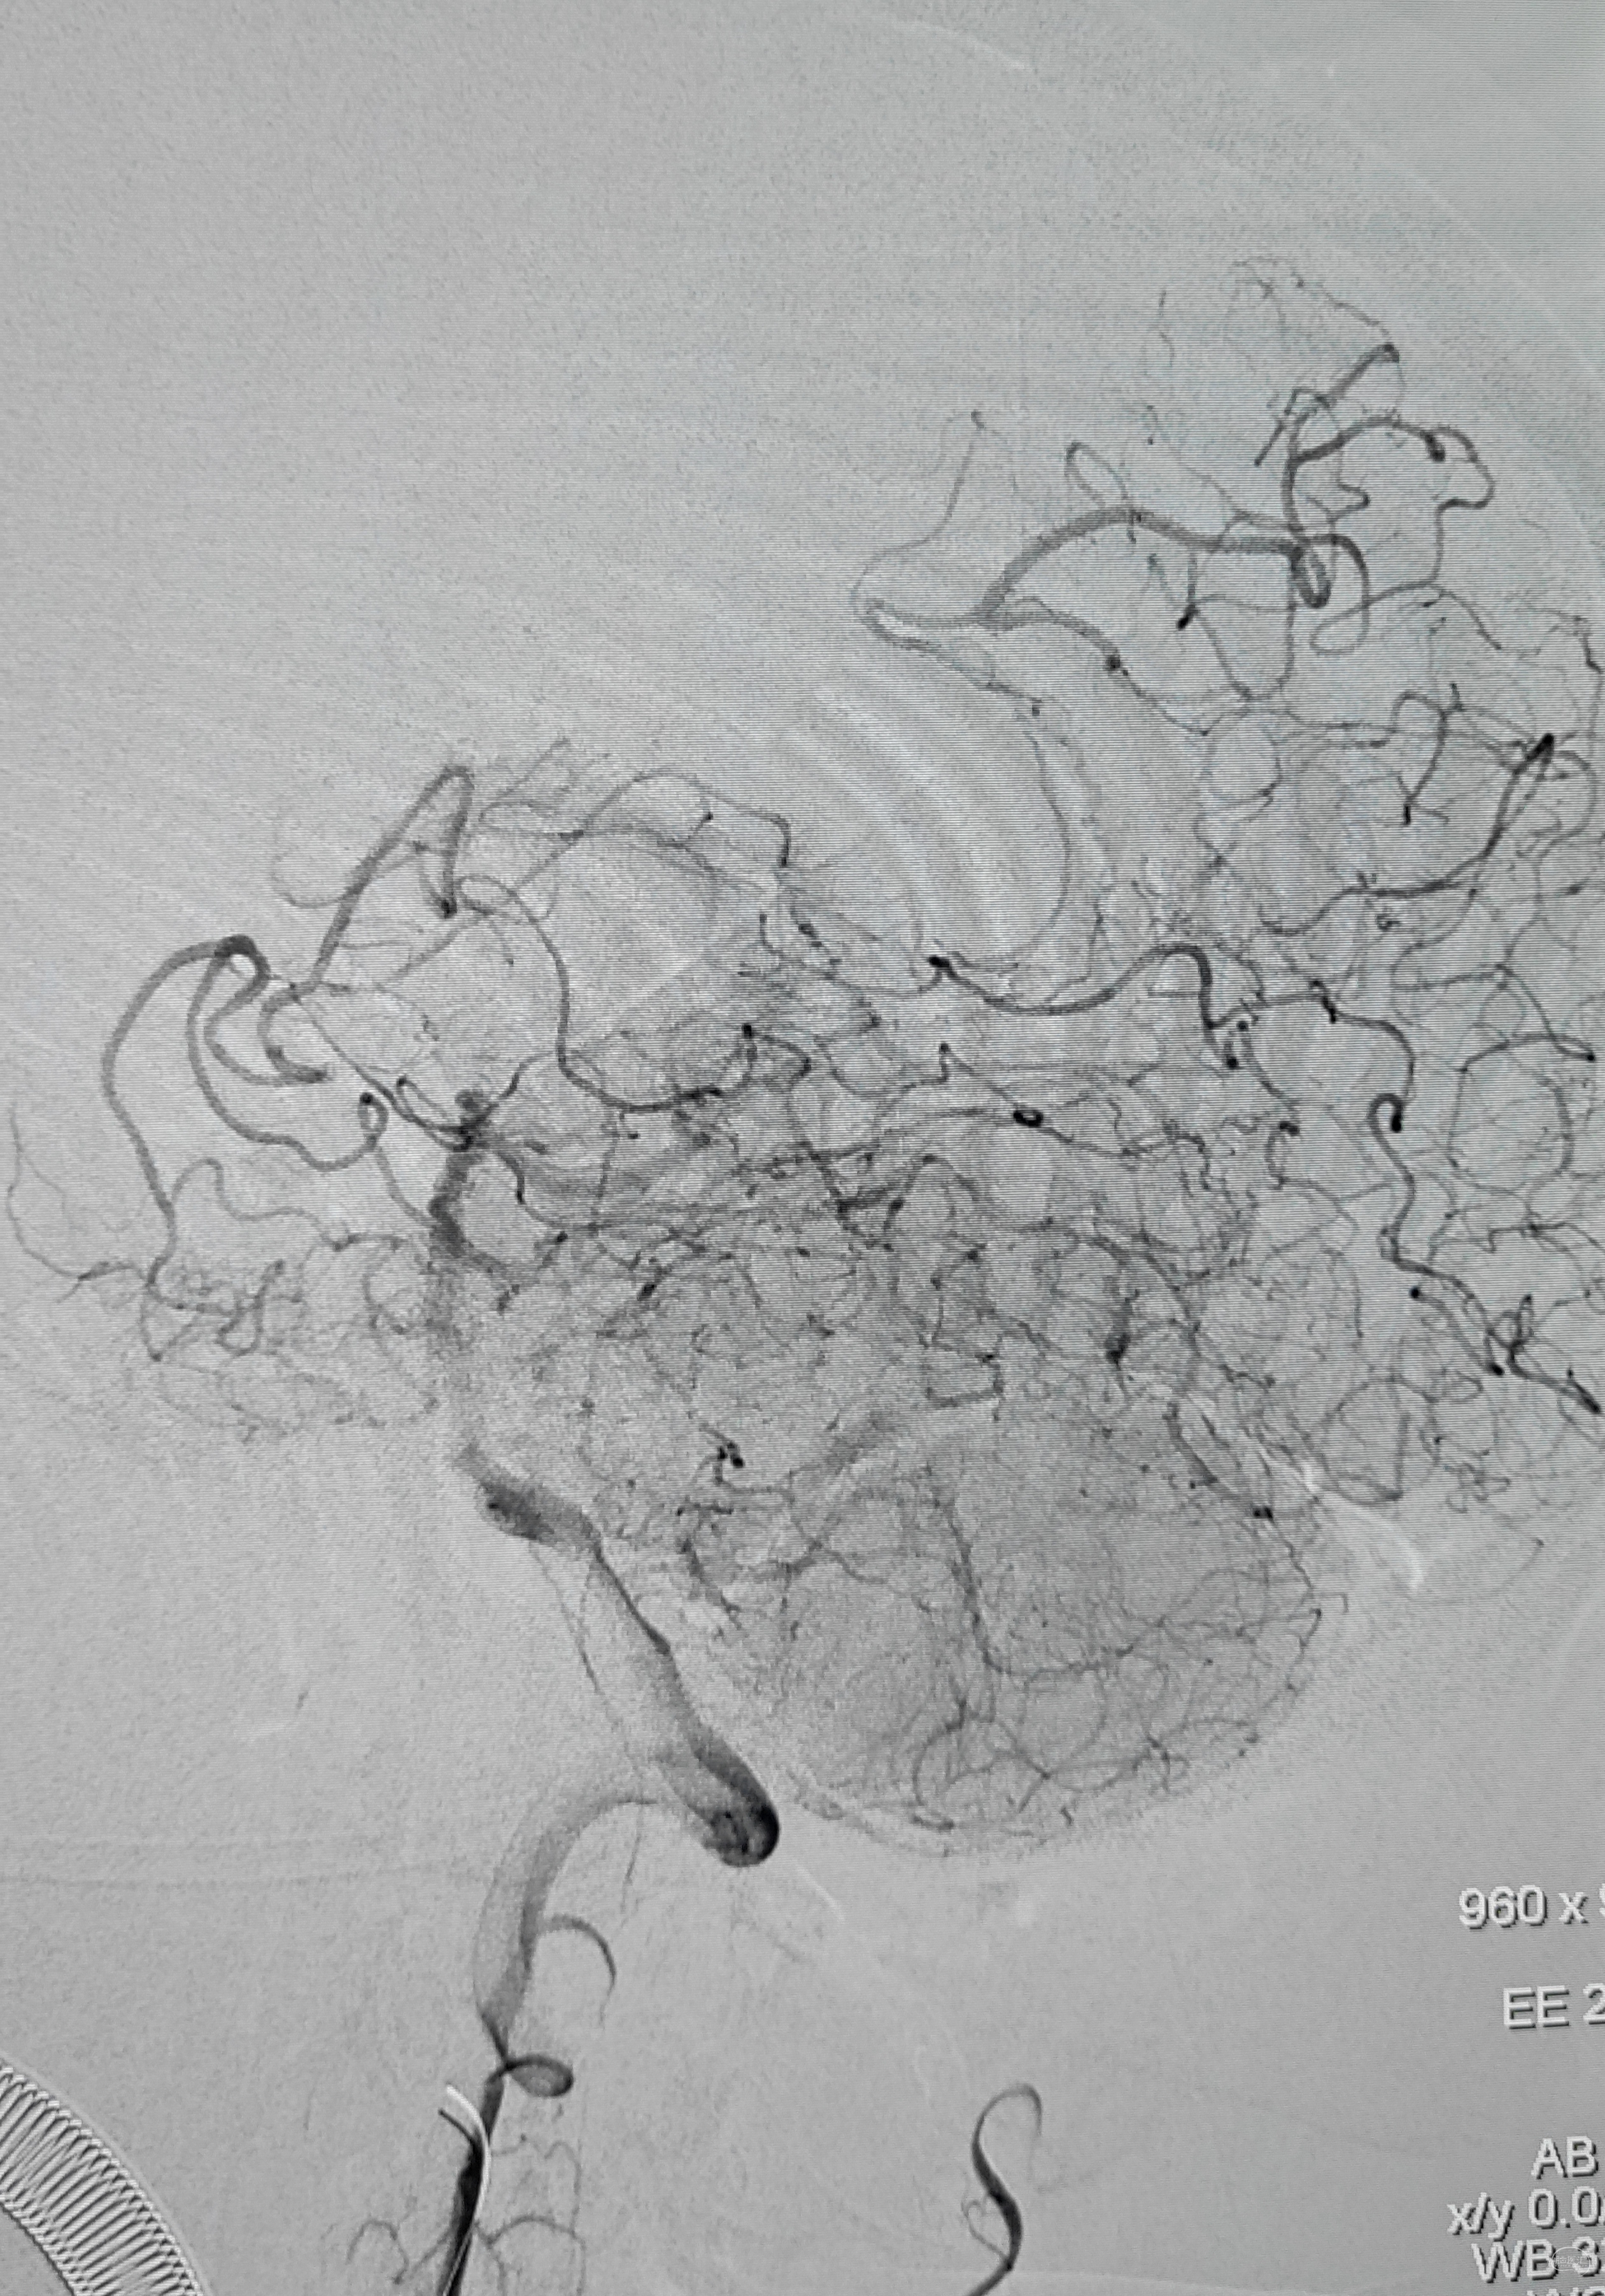

术后即刻造影,右侧椎动脉显影佳,并向左侧前循环代偿供血良好